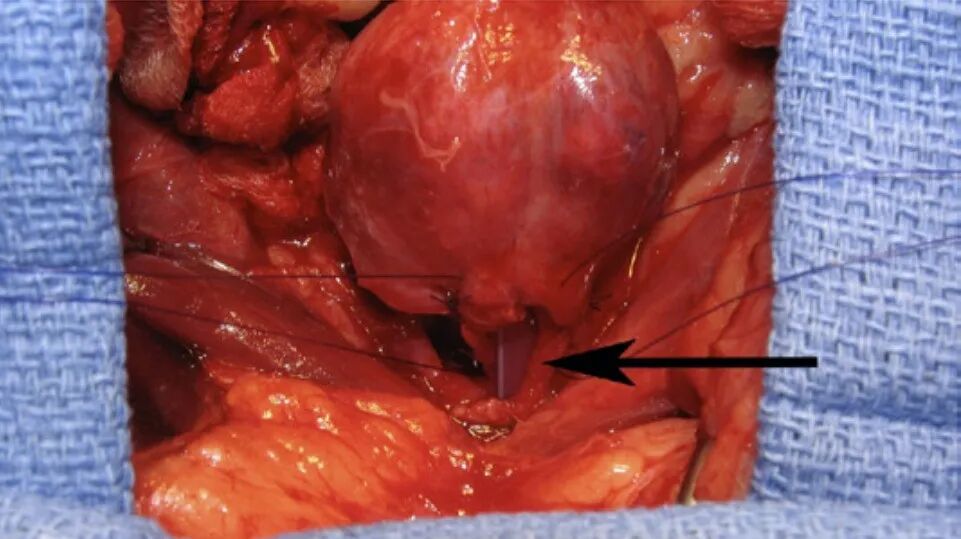

图1.小型至中型犬的放射学研究(A)犬右侧卧位,后肢尾部绑扎拉扯,前肢绑扎拉扯。光标记图像的头侧边界,该边界被准直到刚好位于剑突头侧的水平。手的位置表示在大转子水平的图像的尾部边界。这个腹部适合放在一个片盒中或作为一个侧面图像。(B)一只小犬的右侧腹部x光照片;注意准直图像的头侧位置(头侧到膈顶)和尾侧准直区域到大转子水平。根据横突的叠加(Nike swoosh)以及髂骨翼和肋骨头的叠加,图像被标注为侧面的。(C)特写图像,显示B(黑色箭头)中侧面图像的叠加横突;Nike swooshes是重叠的,尽管横突有轻微的旋转。这种倾斜程度被认为是可以接受的。(D)犬呈腹背卧位,后肢用绷带固定,并从尾部拉动。光标记图像的尾部边界,该图像被校准到股骨大转子的水平。(E)腹背x光照片;注意腹背部图像视野的头部和尾部位置。此外,尾椎肋骨和骨盆结构是对称的,尾椎和腰椎的棘突有一个焦点“泪滴”